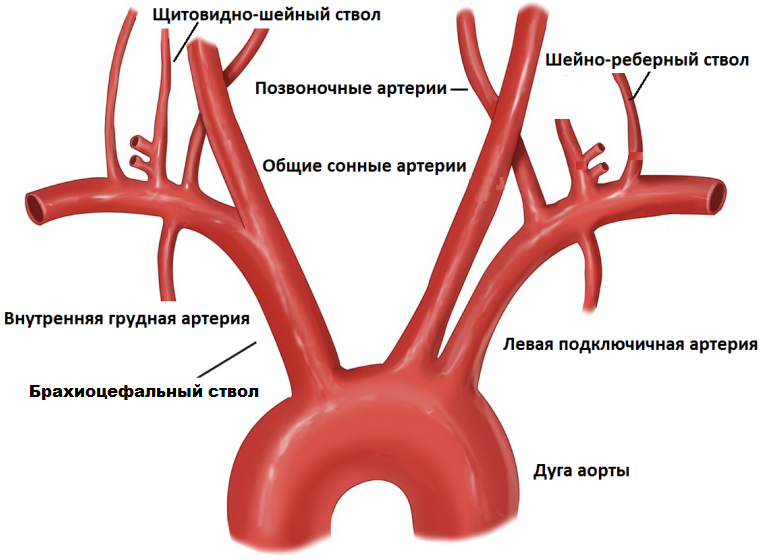

Особенности и диагностика левостороннего кровотока